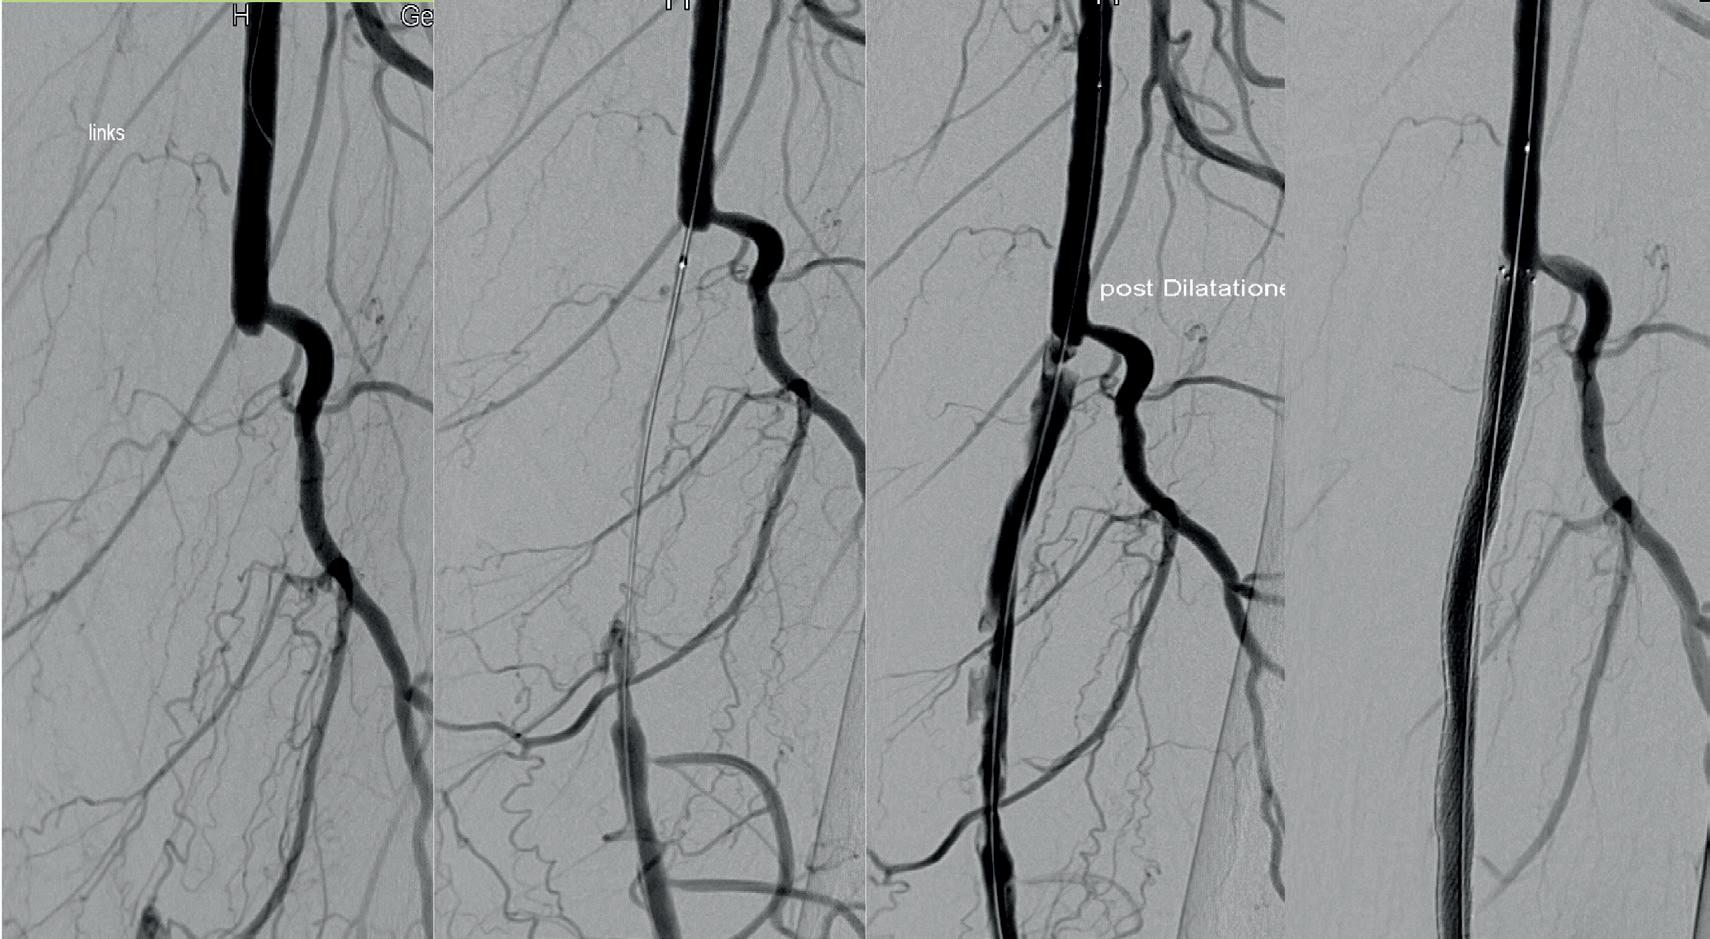

ASE THREE

Female, 83 years old

Uveal melanoma, left eye (A). Right transfemoral catheterisation of the left jugular vein (B, C) with finding of HNF1A mutation indicating a poor prognosis.

Another application of selective venous sampling is in ocular cancers. Uveal melanoma (Case three) can express mutations predicting disease evolution. Follow-up relies on abdominal ultrasound to detect hepatic metastases, which are invariably detected too late for effective treatment. Sampling from the jugular vein on the melanoma side allows molecular characterisation of the tumour, predicting its behaviour and guiding the use of new drugs with recent, promising results. Until now, this tumour has been treated with radiotherapy based on a diagnosis made with physical and radiological means applied to the intact eye.